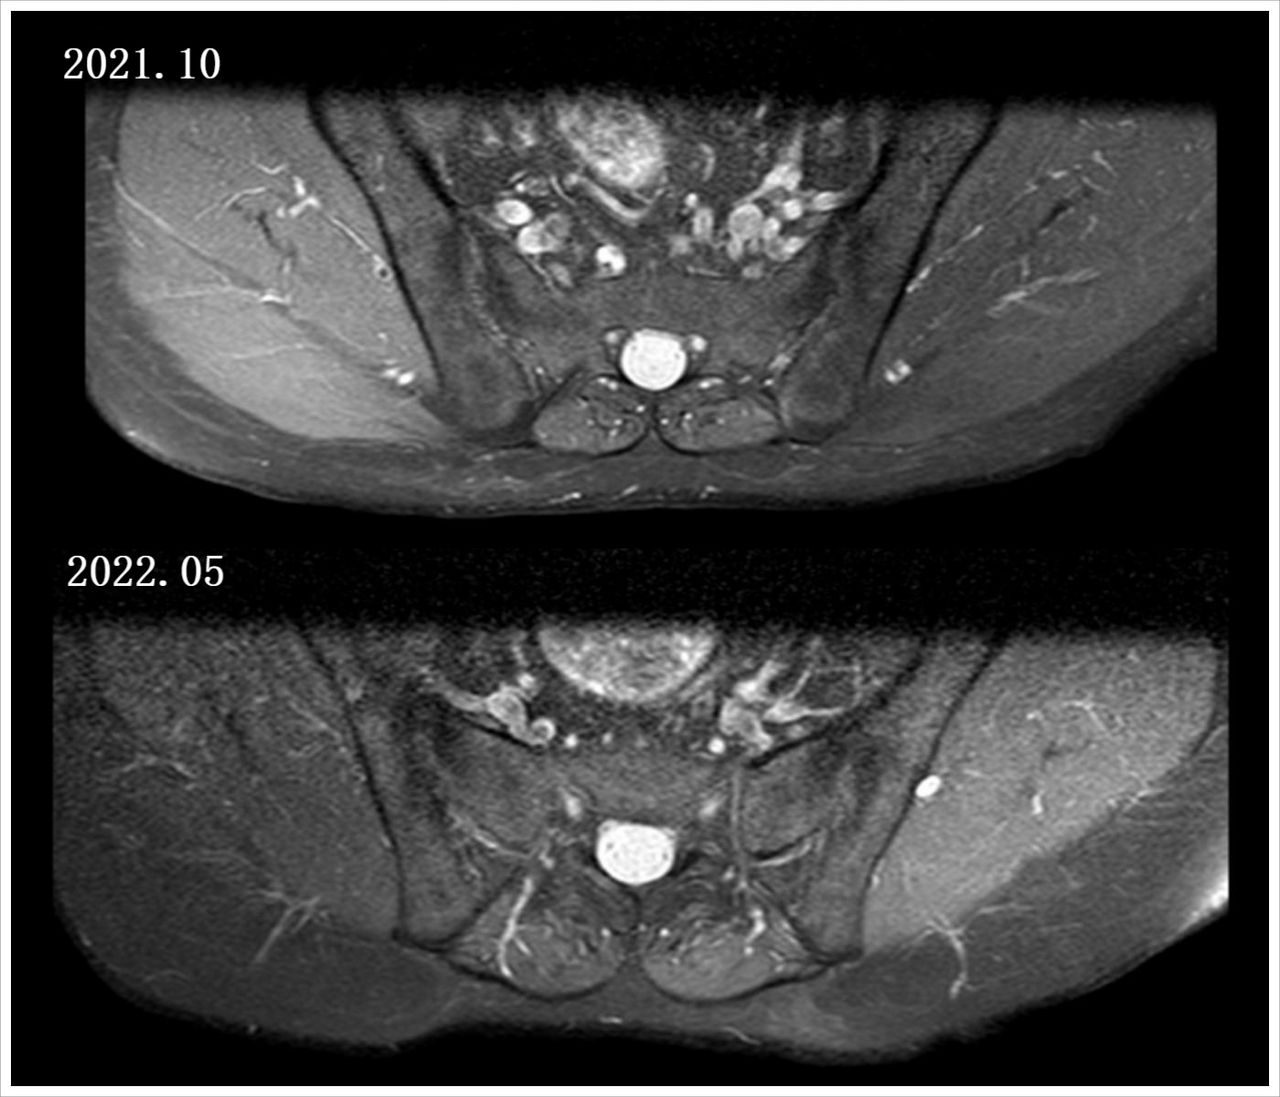

冷先生,47岁。因反复颈腰疼痛导致活动受限已有10年,近半年症状加重。遂于2021年10月9日来我院住院治疗。

DR骶髂关节正位检查提示:腰椎及骶髂关节改变。

2021.10.09—2021.10.15

2021.10.15—2022.01.14

2022.01.15—2022.05

脊柱僵直和肌肉紧张症状已缓解,指标也逐渐下降好转。

患者坚持使用格乐立8个月,症状逐渐好转,好转后病情相较稳定,用药期间无不良反应发生。